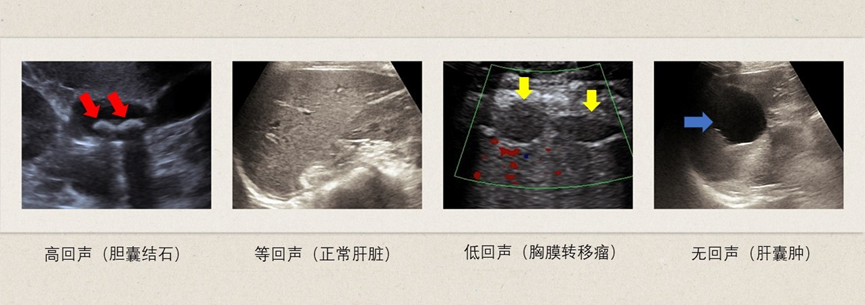

“医生,我这报告上写的‘肝内无回声区’是啥意思啊?是不是长肿瘤了?”诊室里,52岁的张阿姨攥着腹部超声报告,声音里满是焦虑。 原来,张阿姨上周体检做了腹部超声,拿到报告后看到“无回声”“见点状强回声”等字眼,越查网上信息越心慌,连夜挂了号来问清楚。其实,像张阿姨这样看不懂超声报告、被专业术语吓住的人,每天都有很多。今天就用大家能听懂的话,把腹部超声报告里的“密码”一一解开。 先搞懂:超声报告里的“回声”,到底在说啥? 超声检查就像“用声音拍照片”,通过声波碰到不同组织的“反射情况”来判断身体状况,而“回声”就是这些反射信号的“名字”。报告里最常见的4种回声,对应着不同的情况,记好这张“翻译表”就不怕: 高回声/强回声 相当于“反光的镜子”。比正常组织回声强,最常见的是结石(比如胆结石、肾结石,会提示“后方伴声影”)、钙化灶(比如肝内钙化,像身体里长了个“小结石”,大多是旧伤或炎症留下的痕迹,良性)。 等回声 相当于“和皮肤颜色差不多的布料”。和正常组织回声一样,比如某些均匀的结节,容易“藏”在正常组织里,需要医生结合其他检查(如超声造影、增强CT)确认。 低回声 相当于“浑浊的米汤”。比正常组织的回声弱,可能是肝血管瘤(良性)、小的肝结节,也可能是炎症(比如胆囊炎早期)。这种情况需要结合大小、形态进一步判断,不一定是坏东西。 无回声 相当于“清澈的水”。通常是液体成分,比如肝囊肿、肾囊肿、膀胱里的尿液。这类情况大多是良性的,就像身体里长了个“小水泡”,只要不太大、不影响功能,定期复查就行,不用慌。 再拆招:4个最常见的认知误区,别再踩坑! 误区1:囊肿就是肿瘤,早晚要癌变? 真相:囊肿和肿瘤完全是两回事!囊肿是“囊状结构”,里面大多是清亮液体,像“小水泡”;而肿瘤是细胞异常增生形成的“肉疙瘩”,分良性和恶性,需要进一步检查判断。 绝大多数囊肿(如肝囊肿、肾囊肿)是良性的,生长缓慢,只要体积不大、没有压迫症状,定期复查即可。只有极少数特殊类型的囊肿(如复杂性囊肿伴钙化、分隔增厚),需要进一步检查排除异常。 比如张阿姨报告里的“肝内无回声区(考虑囊肿)”,就是良性的,医生让她半年后复查就行,根本不用手术。 误区2:胰腺显示不清,就是胰腺出问题了? 真相:“胰腺显示不清”是超声检查中很常见的情况,大多和检查条件有关,不是胰腺病变的信号。 胰腺的位置较深,前面有胃和肠道遮挡,如果检查前没做好准备(如胃里有气体、没空腹),声波就很难穿透,导致显示不清。这种情况通常会建议“空腹复查”,并非胰腺本身有问题。 误区3:“看到‘见血流信号’,肯定是恶性的?” 真相:错!有血流不代表“不好”,就像“植物需要浇水”,身体组织也需要血液供应。 良性的东西也会有血流:比如肝血管瘤、子宫肌瘤,这些良性病变需要血液维持生长,报告里会提示“可见少量血流信号”,是正常现象。 恶性的东西可能血流“不正常”:比如肝癌,可能会出现“丰富的异常血流信号”(比如血管乱走、血流速度快),但这只是参考,不能单凭“有血流”就断定是恶性。 简单说:“有血流”是常规描述,关键看“血流的多少和形态”,最终得由医生综合判断。 误区4:“报告写‘未见明显异常’,就不用给医生看了? 真相:绝对不行!“未见明显异常”不等于“完全没问题”,有两个关键原因: 1.超声有“盲区”:比如胃里有食物、肠道有气体时,会挡住胰腺、胆囊的视线,可能漏看小问题;而且超声对某些早期肿瘤(如小肝癌)的识别能力有限,可能需要结合抽血(如查肝功能、肿瘤标志物)进一步确认。 2.医生要“结合症状”:比如你明明有腹痛、腹胀,但超声没查出问题,医生会根据你的症状建议做其他检查(如胃镜、CT),而不是只看超声报告下结论。 记住:无论报告是否提示异常,也一定要把报告和体检表一起带给医生,让医生结合你的年龄、病史、症状“综合把关”,才算完成一次完整的体检。 最后划重点:读懂报告的正确姿势 1. 先看“结论” 报告最后通常会有“超声提示”,比如“肝囊肿”“胆囊结石”“未见明显异常”,先抓住核心结论,不用纠结前面的专业描述。 2. 别慌“专业术语” 遇到“无回声”“低回声”,对照前面的“回声翻译表”初步判断,不确定的先标记,再找医生解读,别自行百度对号入座,网上信息繁杂,容易引发不必要的焦虑。 3. 带齐资料找医生 无论报告有没有问题,都要拿给专科医生(比如消化科、肝胆外科)看,复查时记得带上既往的超声报告,方便医生对比病变变化。 4. 重视“建议随访”和“进一步检查” 如果报告提示“定期复查”“建议CT/MRI检查”“建议穿刺活检”,一定要及时遵医嘱执行,这是早发现、早诊断的关键。 腹部超声是最常用的“体检神器”,读懂报告不用成为“专家”,只要避开误区、找对医生,就能轻松应对。下次再拿到报告,别再慌慌张张啦! 作者:胸科医院超声科 杨玲 主治医师